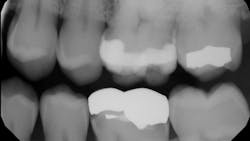

Just this week, I saw a patient for a recare exam who had decay under the mesial margin of a gold onlay I placed seven years ago. I looked back through the sporadic bitewings from the past several years, and sure enough, there it was—small at first and growing as my denial grew with it (figures 1 and 2).

My first inclination was to tell myself that we had made it past the seven-year insurance replacement mark, so it wasn’t a problem. Then, I wanted to blame the patient’s bad habits and inconsistent recare visits. But the professional health-care provider in me knew deep down where the blame was and what I should do. So, I sat the patient up (we’ll call him John) and confessed my sins.